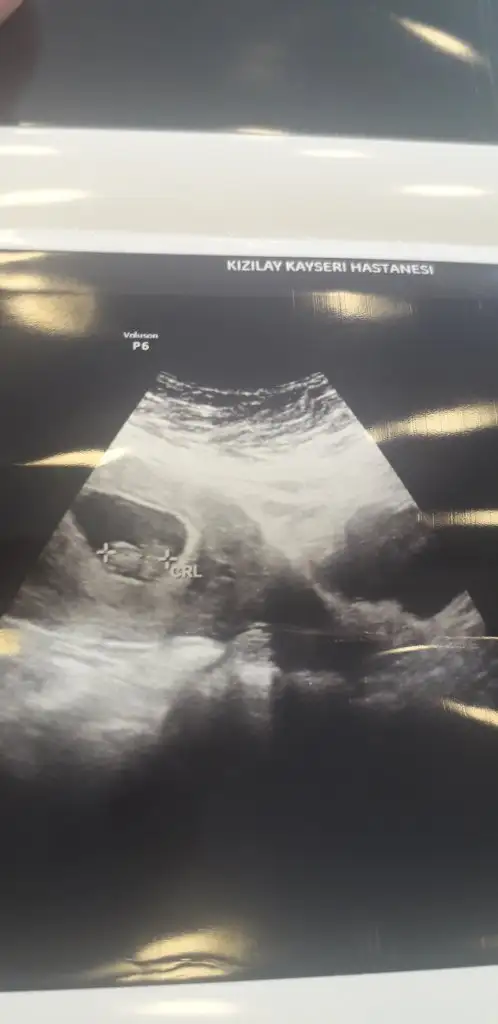

Kızlar banada yorum yapar mısınız 6 haftalık görüntüsü karından